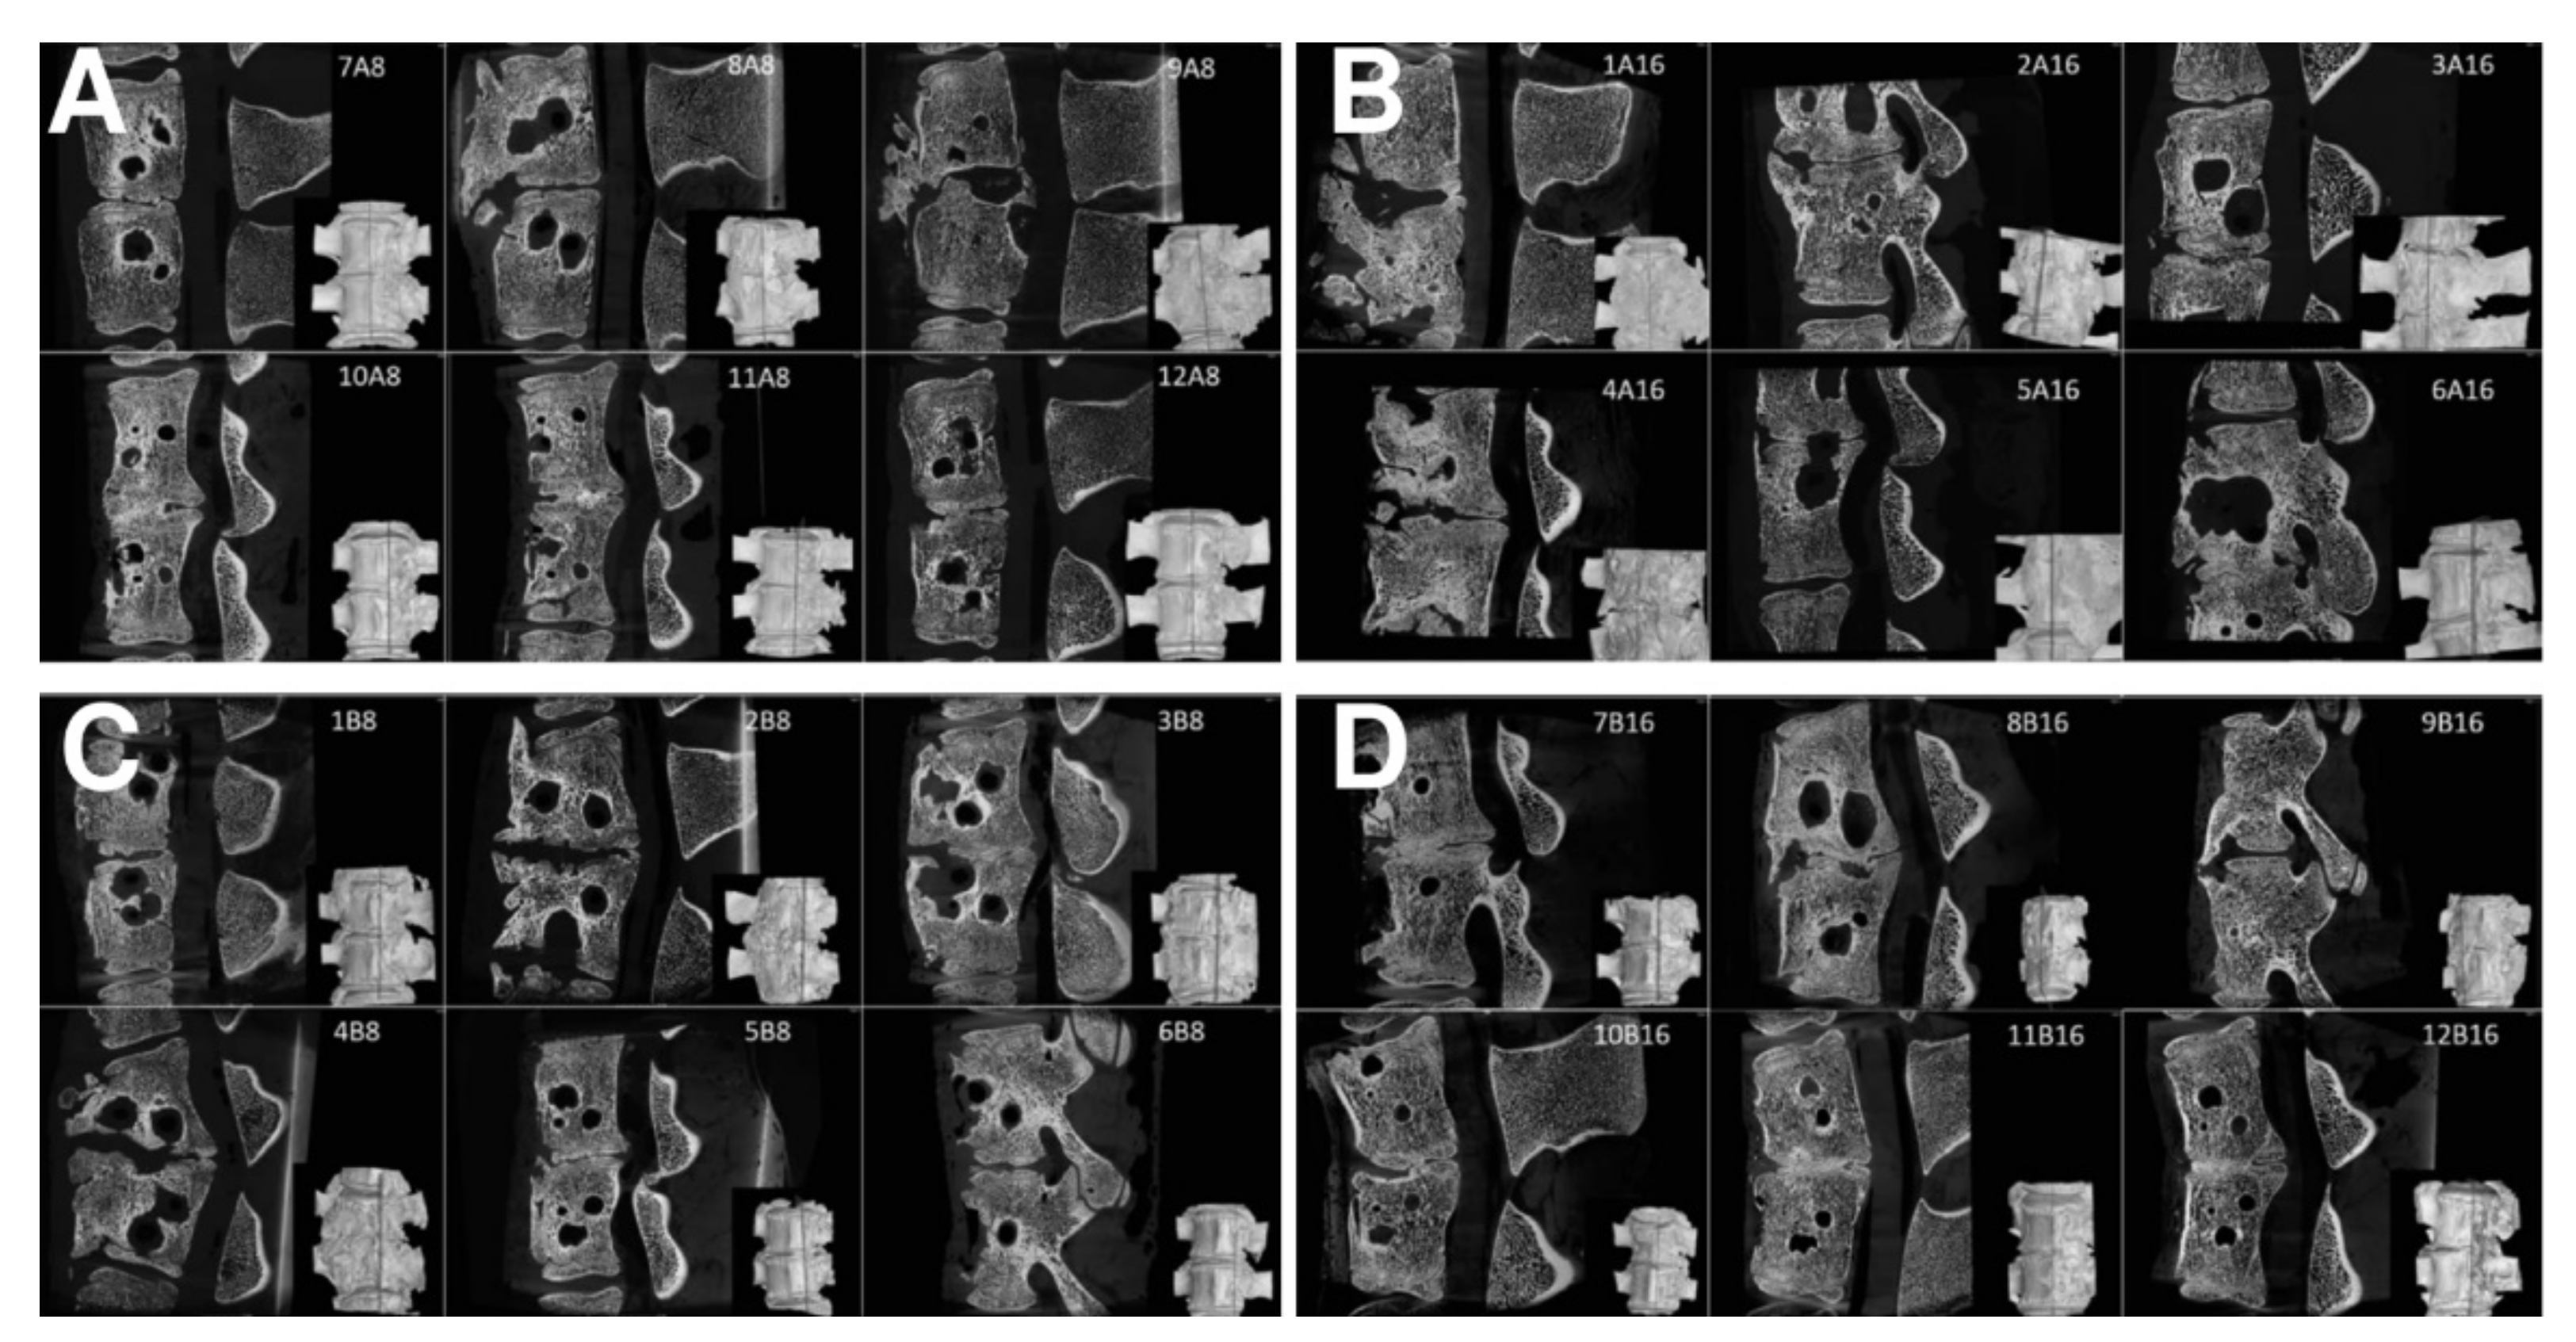

3.4. Micro-CT

3.5. Histology